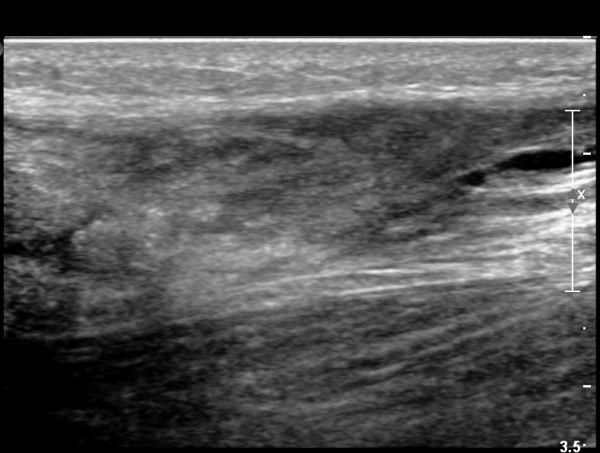

2018³â  1¿ù 30ÀÏ ÃßÀû°Ë»ç

¾ÆÅ³·¹½º°Ç Àú¿¡ÄÚºÎÁ¾ÀÌ °¨¼ÒµÇ°í  ÆÄ¿­ºÎÀ§ Àú¿¡ÄÚ°¡ È£ÀüµÇ¾î

°ÇÀÇ ¼¶À¯¼º¾ç»ó(fibrillar pattern)ÀÌ È¸º¹µÇ°í ±¹¼ÒÀû ¿¬°á¼º ¼Ò½ÇÀÌ »ç¶óÁü(»çÁø 9, 10, 11, 12).